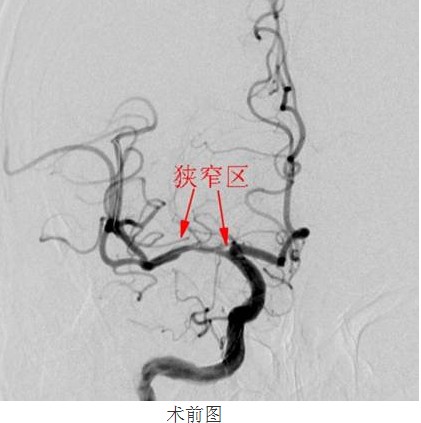

經(jīng)過數(shù)天的積極治療,患者行頭顱MRI+MRA檢查,結(jié)果和顏醫(yī)生判斷一致:右側(cè)基底節(jié)區(qū)額、頂、顳、枕葉白質(zhì)區(qū)腦梗塞,腦動(dòng)脈硬化,右側(cè)大腦中動(dòng)脈M1段不規(guī)則重度狹窄,分支血管減少。為了進(jìn)一步明確右側(cè)大腦中動(dòng)脈狹窄的程度及其他腦血管代償能力,是否達(dá)到神經(jīng)介入治療的指征,21顏津津主治醫(yī)師醫(yī)生為患者進(jìn)行了DSA腦血管造影(判斷血管狹窄的金標(biāo)準(zhǔn))進(jìn)一步證實(shí)磁共振檢查提示,右側(cè)大腦中動(dòng)脈M1近端狹窄,程度約80%,長度約12cm

113患者被送進(jìn)了DSA室內(nèi),在南方醫(yī)科大學(xué)劉亞杰教授的指導(dǎo)下,患者在靜脈全麻下(在麻醉科龍宏杰主任積極配合下),行“右側(cè)大腦中動(dòng)脈血管成形及支架植入術(shù)”。

常規(guī)準(zhǔn)備后,神經(jīng)內(nèi)科顏津津主治醫(yī)師在助手高彬醫(yī)師配合下采用Seldinger法穿刺股動(dòng)脈,置導(dǎo)管鞘、引導(dǎo)管,在導(dǎo)絲帶引下將導(dǎo)引導(dǎo)管放置右側(cè)頸內(nèi)動(dòng)脈巖部造影,后在透視下,順著造影路圖,小心將微導(dǎo)絲、微導(dǎo)管通過狹窄處并置入右側(cè)大腦中動(dòng)脈M3段,接著撤出微導(dǎo)管,順著微導(dǎo)絲置入Gateway球囊, 至狹窄部位,經(jīng)造影骨性標(biāo)志等多重定位后證實(shí)球囊位置良好,接壓力泵緩慢加壓擴(kuò)張,撤出球囊造影,顯示血管成形良好。選取Wingspan支架, 順微導(dǎo)絲將支架輸送器小心送至狹窄處,造影定位確認(rèn)支架位置準(zhǔn)確覆蓋狹窄部位,釋放支架,撤出支架輸送器,造影證實(shí)血管狹窄處成形良好,觀察10分鐘后再次造影,支架無移位,狹窄處遠(yuǎn)端血管完整,未見血管狹窄、造影劑外滲。撤除導(dǎo)絲、導(dǎo)引導(dǎo)管,患者術(shù)后24小時(shí)可下床自行活動(dòng),術(shù)后1周順利出院,生活基本恢復(fù)正常,并叮囑梁伯繼續(xù)堅(jiān)持服藥,定期復(fù)診。